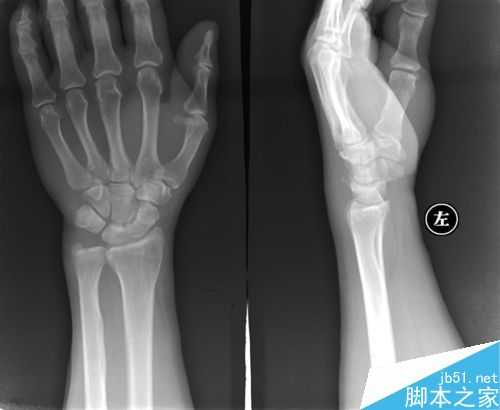

鼠标手是一种病程很长的疾病。前期的鼠标手可以自愈,如果得了鼠标手却满不在乎,那么拖到后期了,就会变成一种顽症,想要彻底治愈,只能通过手术的方式了。

鼠标手